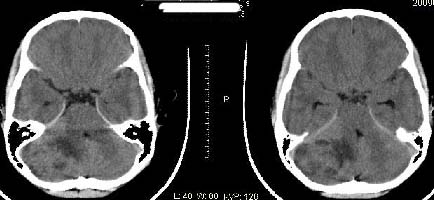

以下是引用子期在2009-6-10 21:34:00的发言:[br]髓母细胞瘤一般位于中线附近和小脑蚓部,该病灶位于右侧小脑半球,倾向于毛细胞型星形细胞瘤,当然也不能完全排除髓母细胞瘤。

以下是引用随光逐影在2009-6-10 22:26:00的发言:[br]考虑右侧小脑胶质瘤,髓母细胞瘤待排。

以下是引用影象小泰斗在2009-6-10 22:14:00的发言:[br]年龄及影像表现军符合小脑星形细胞瘤表现![br]期待病理结果!